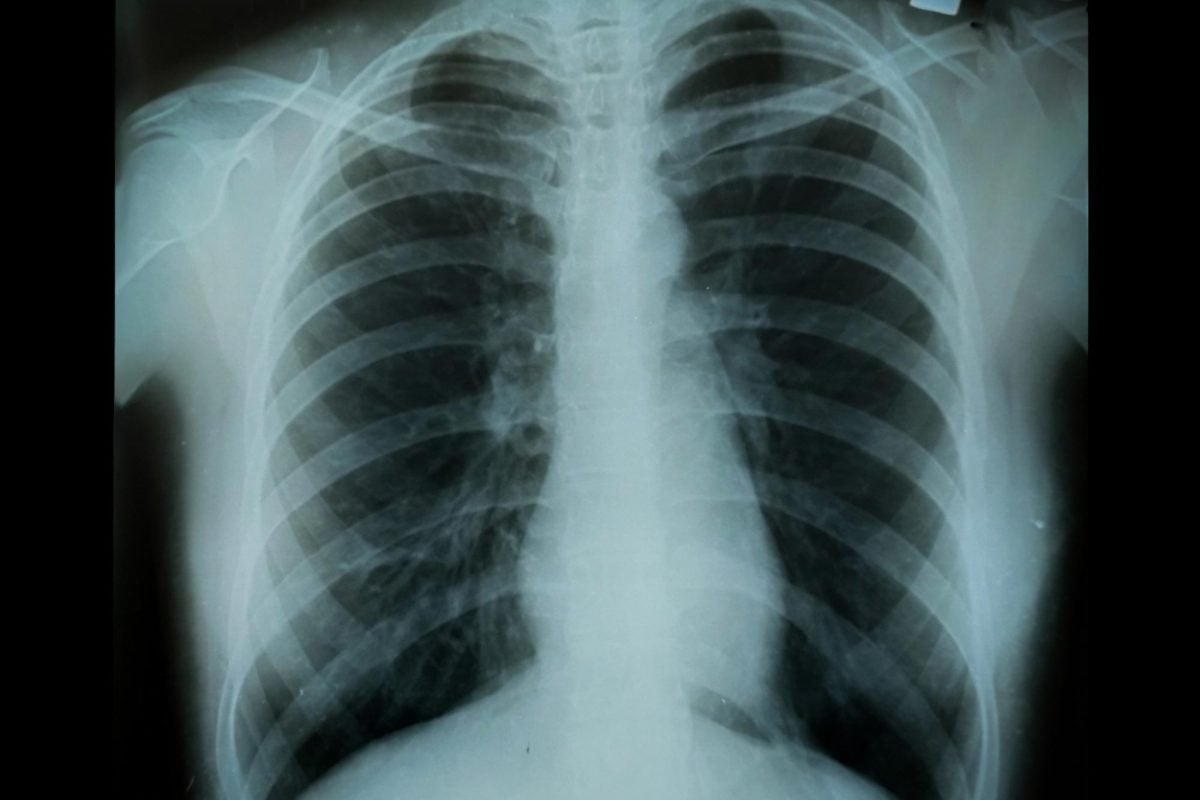

Pulmonary Conditions That Cause Painful Breathing

Breathing is essential for life, but some lung issues can make it painful. Feeling pain when you take a deep breath might signal a serious problem. It’s important to get medical help if this happens.

Pneumonia and Respiratory Infections

Pneumonia and other lung infections can cause lung inflammation, leading to breathing pain. These infections can be from bacteria, viruses, or fungi. Symptoms include coughing, fever, and shortness of breath. Knowing the cause is key to the right treatment.

Lung Cancer and Breathing Pain

Lung cancer can also cause chest pain, often if the tumor affects the lung’s lining. The pain might feel like a dull ache or sharp stabbing that gets worse with deep breaths or coughing. Finding and treating lung cancer early is critical for better outcomes.

If you have ongoing or severe chest pain while breathing deeply, see a doctor. They can find out what’s causing it and help you get better.